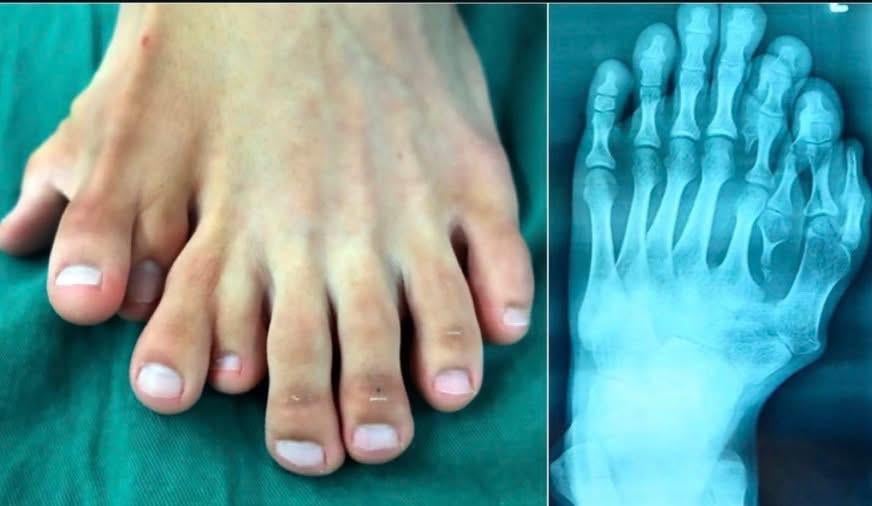

Rare case of (Mirror Foot )polydactyly (with X-ray). It’s like his foot tried to clone itself.

Mirror foot polydactyly, also called duplication of the foot or lateral ray polydactyly, is an extremely rare congenital deformity where the foot develops extra toes—often in a symmetrical, mirrored pattern—alongside duplicated bones (metatarsals and phalanges). Unlike simple polydactyly (a single extra digit), mirror foot involves duplication of entire rays of the foot, creating an intricate, split-like appearance.

X-rays of mirror foot polydactyly reveal a surreal, symmetrical duplication of bones—as if the foot attempted to clone itself. The central axis of the foot often splits into mirrored halves, with duplicated metatarsals and phalanges fanned outward.